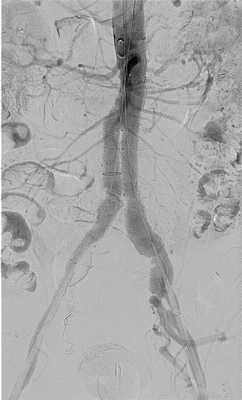

Аортография. Более травматичным, но у ряда больных совершенно необходимым, методом исследования является аортография (рис. 17.1). Она показана в клинически неясных случаях с целью установления окончательного диагноза. Но даже при установленном диагнозе разрыва АБА рентгеноконтрастное исследование дает ценную дополнительную информацию: 1) определение взаимоотношений аневризмы с висцеральными ветвями брюшной аорты, ее распространения на бифуркацию аорты и подвздошные артерии; 2) уточнение характера окклюзионных поражений висцеральных артерий и магистральных артерий конечностей; 3) выявление аортокавального свища. Следует отметить, что при аортографии не всегда удается подтвердить факт разрыва аневризмы, так как экстравазации контрастного вещества может не быть в связи с тампонадой дефекта стенки аневризматического мешка кровяными сгустками. Противопоказанием к аортографии является крайняя тяжесть состояния больного и нестабильная гемодинамика со снижением артериального давления ниже 90 мм рт.ст.